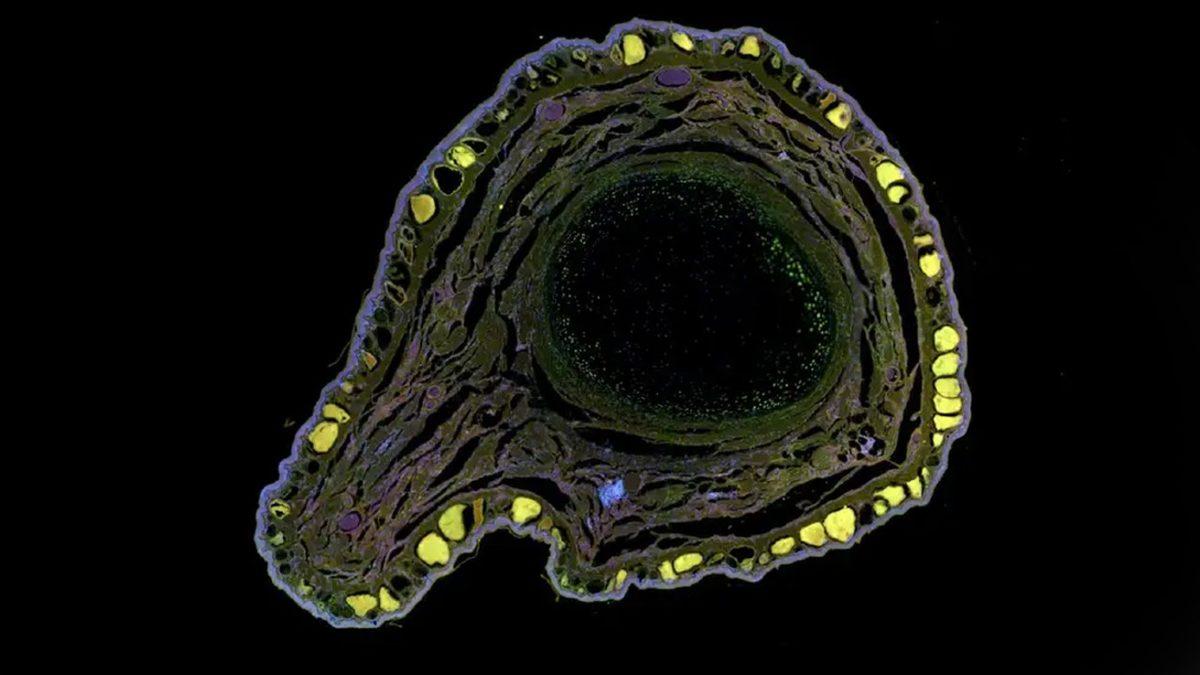

Rejenerasyon yeteneğine sahip hayvanlardan biri ise Xenopus laevis ismi de verilen Afrika pençeli kurbağası. Ancak bu tür, yalnızca iribaş (yavru) iken uzuvlarını yenileyebiliyor. Yetişkinlikte ise bu yetenek kaybediliyor. Harvard ve Tufts Üniversitesi’nden bilim insanları da bu kurbağalara yönelik bir ilaç geliştirerek kaybedilen uzuvların geri kazanılmasını sağladı.

‘Yenileyici tıbbın hedeflerine yaklaşmada önemli bir adım’ olarak tanımlanan araştırmada, kurbağanın ampute olan bölgesine rejeneratif ilaç karışımı içeren bir silikon başlık yerleştirildi. Ardından bu başlık 24 saat boyunca eksik bölgede bekletildi. Yapılan 18 aylık gözlemler sonucunda da kaybedilen uzvun bulunduğu bölgede kas, kemik ve çıkıntılardan oluşan yeni bir yapının oluştuğu gözlemlendi.